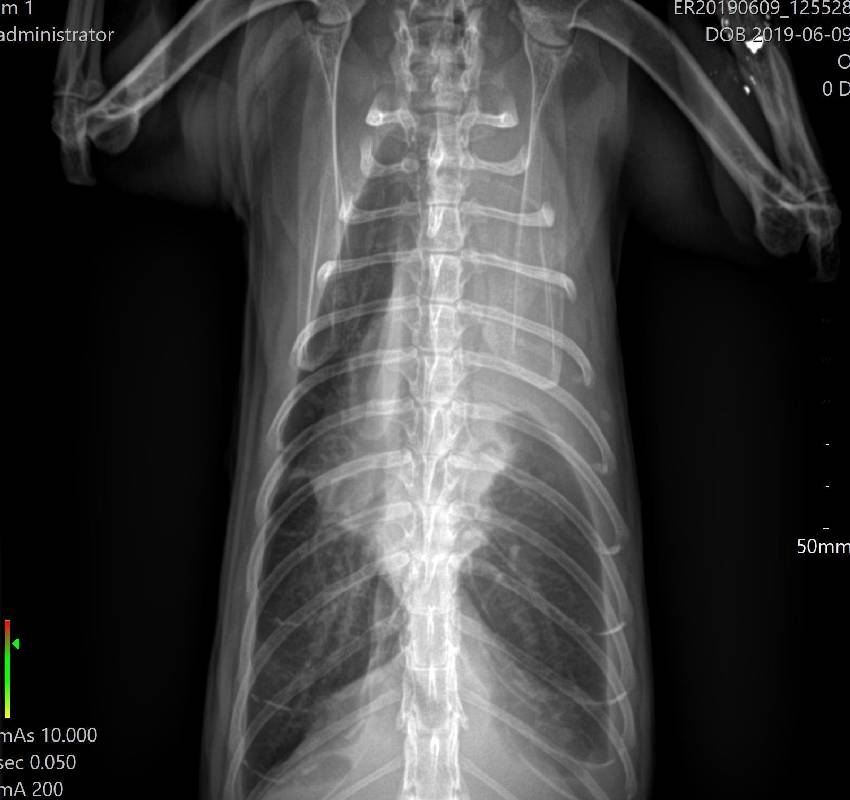

When your pet is under the weather we do everything we can to find out what is causing it’s hardship. While a thorough history and physical exam are solid steps towards diagnosing your pet’s condition, we sometimes rely on radiographs (x-rays) to provide valuable information about a pet’s internal organs. Radiographs can provide a more comprehensive view of the abdomen, chest and bones aiding in the diagnosis of a number of conditions including fractures, foreign bodies and bladder stones. State-of-the-art digital radiograph technology provides several benefits for our patients, staff and even our clients.

• Images are produced within seconds meaning a quicker diagnosis and less wait time for your pet.

• Images can be shared digitally with referral centers, emergency clinics or radiologists if needed

• Less radiation is used meaning a safer environment for your pet and our staff.

Digital Radiology (x-rays)